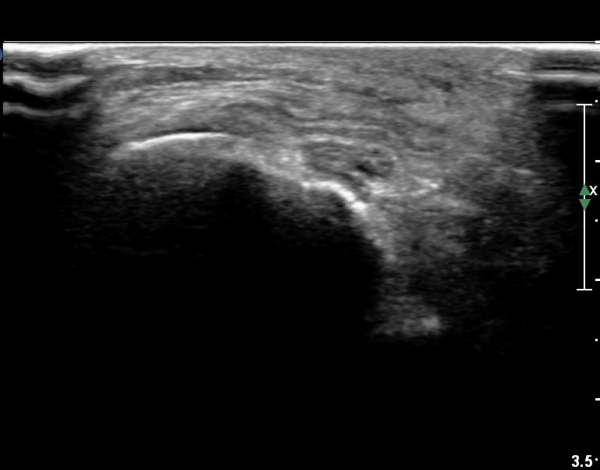

¹«¸­ ¿À±Ý ºÎÀ§ Ⱦ´Ü¸é°Ë»ç¿¡¼­ °æ°ñµ¿¸Æ Ç¥Ãþ¿¡ ºñ°ñ½Å°æ°ú °æ°ñ½Å°æÀÌ ºÐ¸®µÇ¾î °üÂûµÈ´Ù(»çÁø 1).

ŽÃËÀÚ¸¦ ¸»´ÜÀ¸·Î À̵¿ÇÏ´Ï À̵ιڱ٠³»Ãø¿¡¼­ ºñ°ñ½Å°æ¿Í °üÂûµÈ´Ù(»çÁø 2).